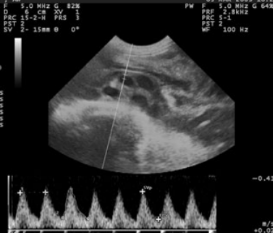

羊用B超机对冠臀长(CRL)测量定

冠臀长通常被认为是可靠的脚气测定法中的参数。测量应为从牙冠(头骨的***上部)取到的臀部(结束的ac骨)(图1和2)什么时候的胎儿完全伸展。GA和CRL之间的高度相关性在不同品种的***个和第三个中期。CRL是确定GA的可靠参数(r=0.99)早怀孕。得出了一个新公式,发现是确定GA的方法非常准确:y=24:42+0:39X其中Y=胎龄,X=CRL。但是,无法执行此测量随着怀孕的进行准确;较低的错误高山山羊胎儿有相关系数的报道在妊娠第33天至146天之间。

图1胎儿上冠状臀围长度的超声图像妊娠40天

图2 胎儿上冠状臀围长度的超声图像妊娠55天